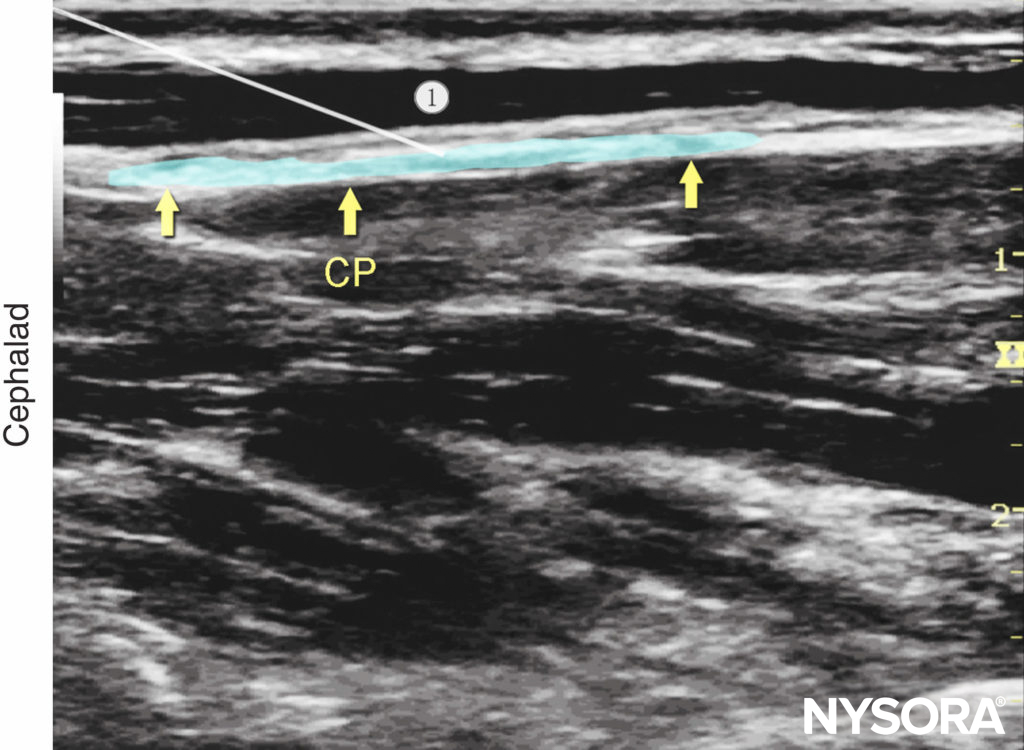

If the plexus is not visualized, an alternative sub sternocleidomastoid approach may be used. In this case, the needle is passed behind the SCM, and the tip is directed to lie in the space between the SCM and the prevertebral fascia, close to the posterior border of the SCM (Figures 7b, 10 and 11). Local anesthetic (5–15 mL) is administered and should be visualized layering out between the SCM and the underlying prevertebral fascia (Figure 12). If the injection of local anesthetic does not appear to result in an appropriate spread, needle repositioning and further injections may be necessary. Because the cervical plexus is made up of purely sensory nerves, high concentrations of local anesthetic are usually not required; ropivacaine 0.25–0.5%, bupivacaine 0.25%, or lidocaine 1% is a sufficient

Figure 12. Cervical plexus (longitudinal view): desired spread of local anesthetic under the deep cervical fascia to nerve block the cervical plexus (CP).